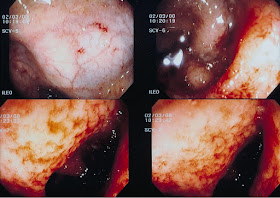

Nas figuras 1 e 2 podem ser

observados os aspectos de mucosa retal normal à microscopia óptica comum,

enquanto que nas Figuras 3-4-5 e 6 podem ser observadas as distribuições

dos eosinófilos nas diversas camadas da mucosa retal nos pacientes com Colite Alérgica.

Figura 3- Colite eosinofílica: notar presença de eosinófilos no epitélio e em grande

quantidade na lâmina própria.

Figura 4- Colite eosinofílica:

notar presença de eosinófilos em grande quantidade no epitélio e na porção

superior da lâmina própria próxima ao epitélio.

Figura 5- Colite eosinofílica: eosinófilos infiltrando o epitélio e na lâmina própria

da mucosa retal.

Figura 6- Colite eosinofílica: notar a presença de eosinófilos na muscular da mucosa.